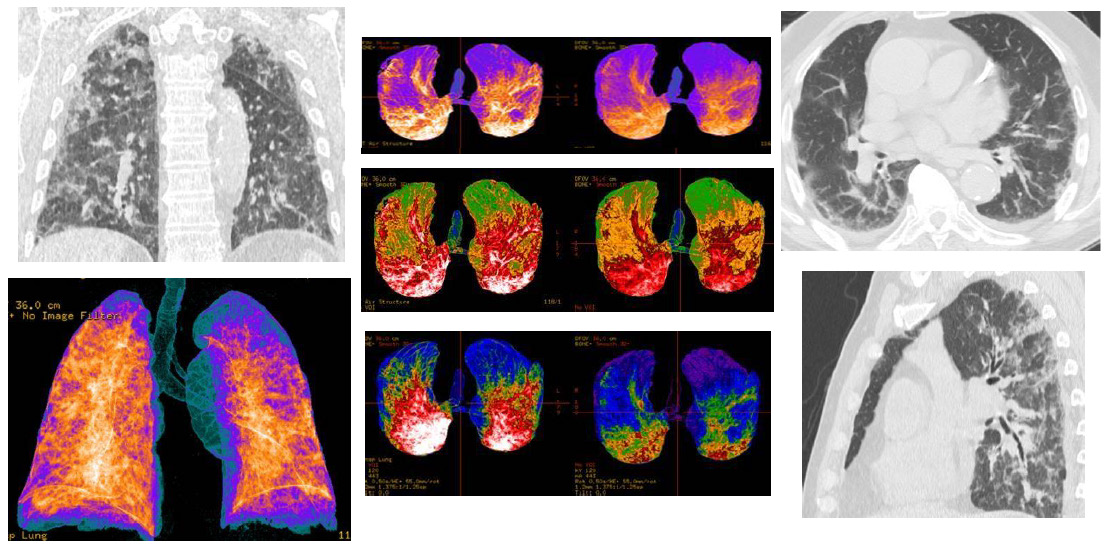

Covid-19, acronym of the English Coronavirus Disease 19, also known as SARS-CoV-2 acute respiratory disease or coronavirus disease 2019, is an infectious respiratory disease caused by the virus SARS-CoV-2 belonging to the coronavirus family. The Covid-19 Coronavirus infectious pandemic started since December 2019. It caused mainly bilateral interstitial pneumonia in the patients. The heterogeneity of the course and clinical frameworks of the disease represents an important problem both for the acute phase and for the possible complications. Imaging Computed Tomography (CT) had a key-role in the diagnosis and follow-up, allowing an optimal management for the patients [1,2]. Many typical imaging features of the pneumonia were described: bilateral multilobar ground-glass opacity (GGO), with a peripheral or posterior distribution, mainly in the lower lobes; consolidative areas of the lungs; septal thickenings; pleural thickenings; subpleural involvements and pleural effusion [3,4]. The 3D-Volume Rendering Reconstructions at the CT of the lungs represent an important and superior model to evaluate the pulmonary envolvement by Covid-19 and is currently being used in support of “classic” CT reconstruction (MPR, MIP) as a guidance for the evaluation in their complexity of the patients affected by Covid-19 pneumonia (Figure 1-3).

Figure 1: CT patterns of bilateral Covid-19 pneumonia of a 75-year-old male patient. In the upper line, MPR (axial, coronal, sagittal) reconstructions, that showed bilateral typical “ground-glass” areas, with interstitial thickenings. In the line above, Volume Rendering (VRT) “colored” reconstructions, that indicated as blue the areas representing the normal lung parenchyma, while orange/white areas indicate the inflammatory pulmonary involvements.